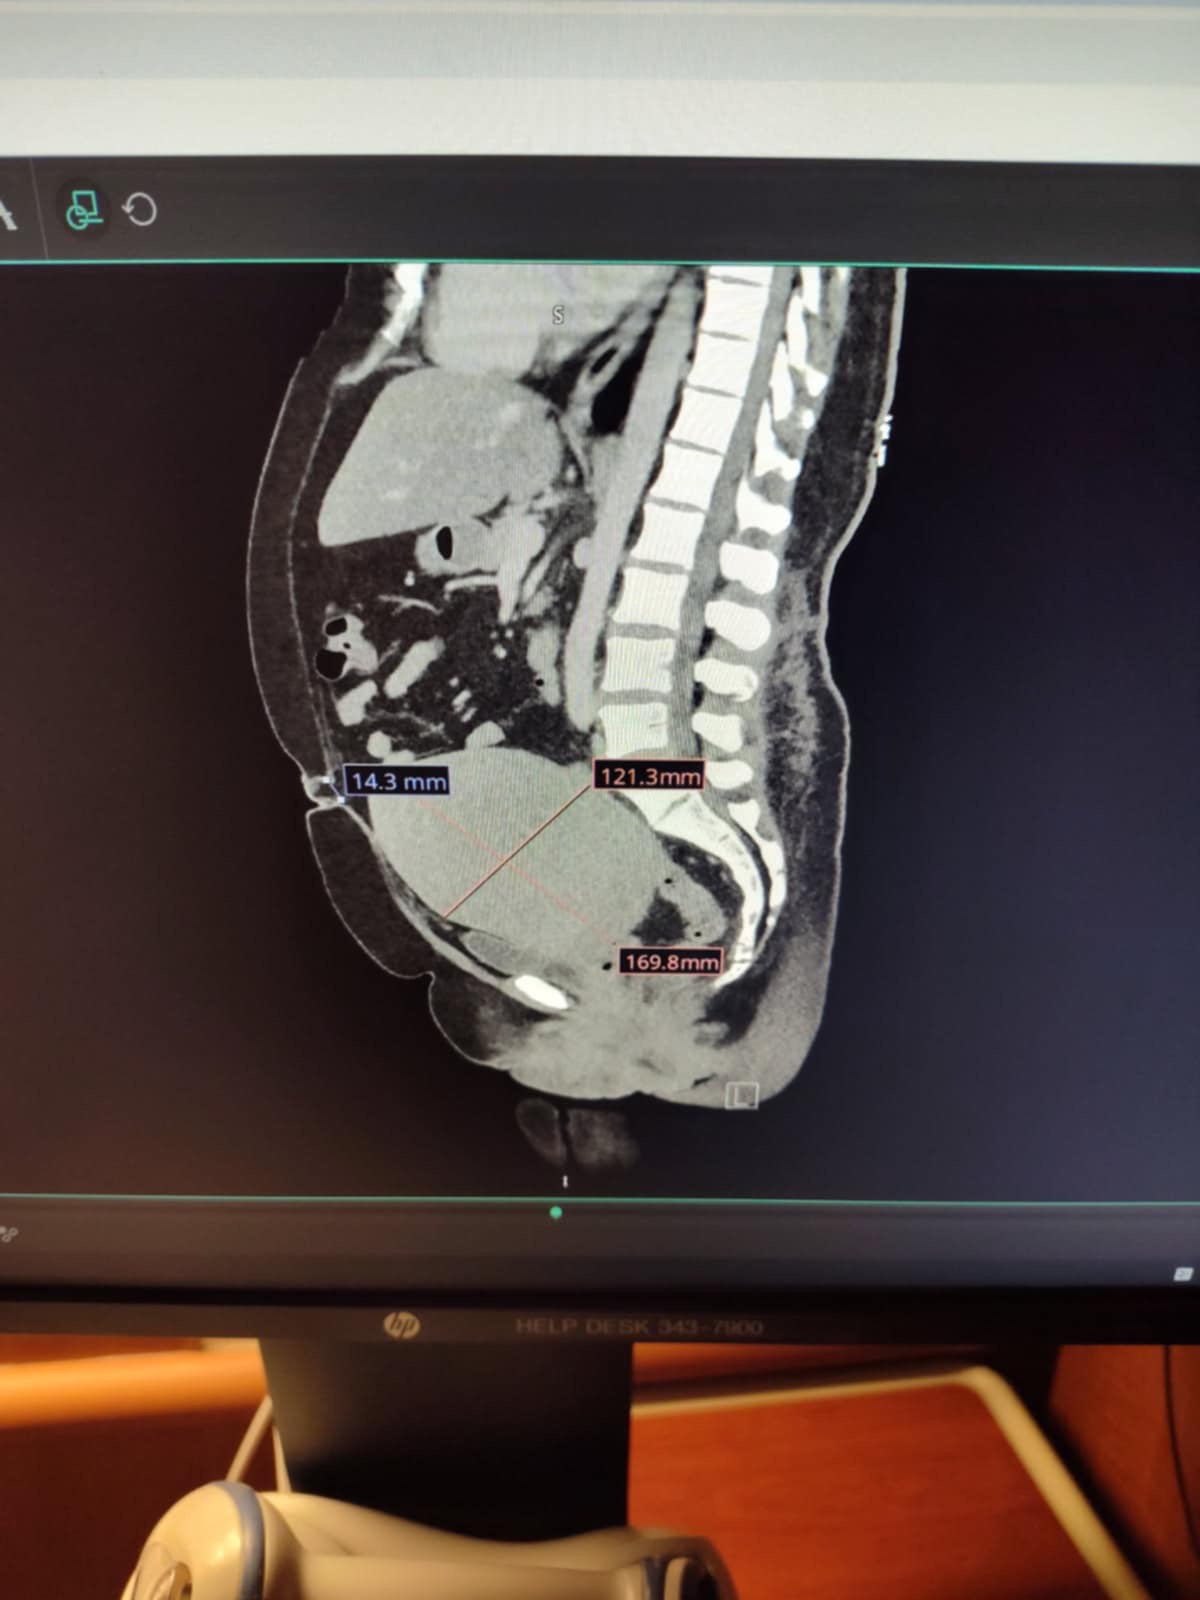

Hello everyone, my name is Melissa and I am in desperate need of a hysterectomy and an umbilical hernia repair surgery. I need to have both surgeries at the same time. My uterus is the size of a basketball and needs to be removed because it’s pressing against all my vital organs and main vein.